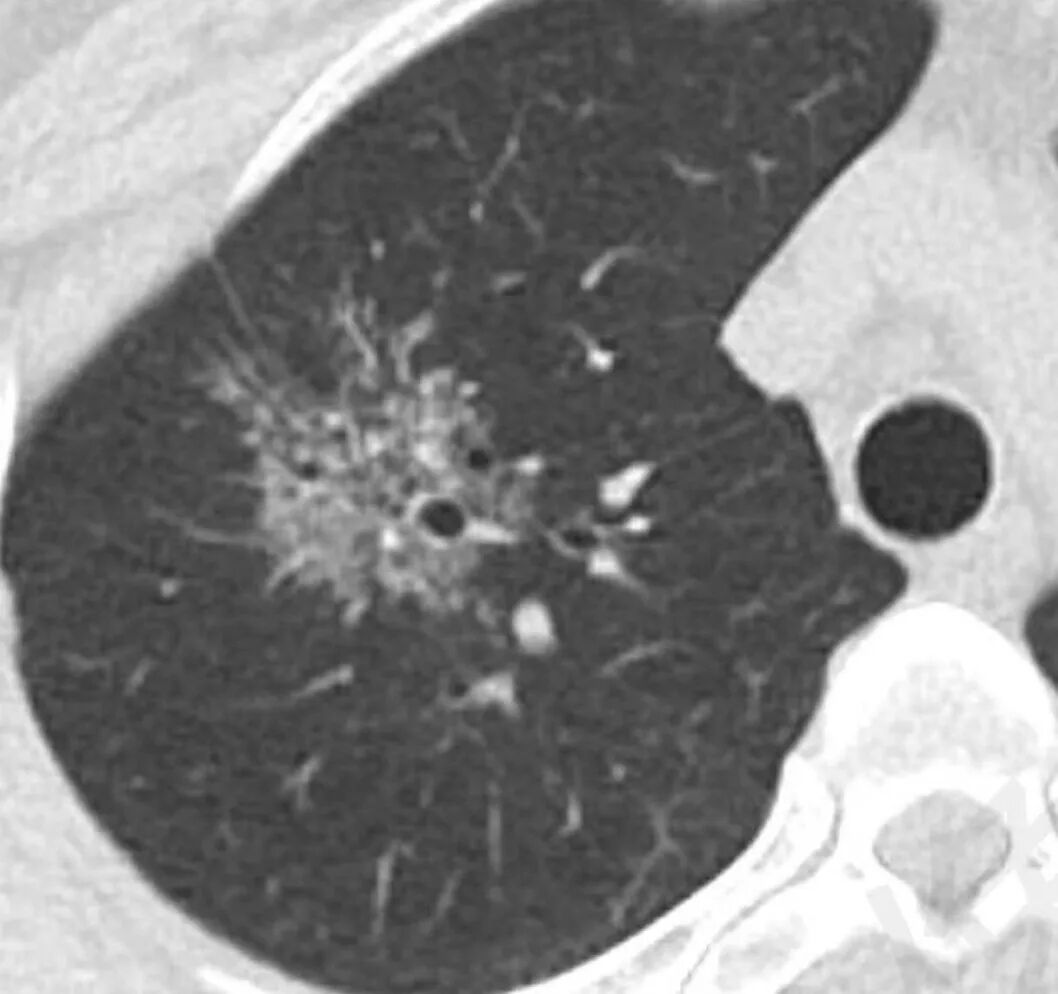

影像特点:右肺上叶混合磨玻璃影,边界清晰,结构松散,内有多结节堆积及支气管扩张影,可见小叶间隔增厚,并局部增厚的小叶间隔上亦存在微结节,胸膜侧可见纤细索条,病灶周围可见多发微结节影。

总体分析:从病灶分布来看符合结核的好发位置,影像表现也符合结核的多态性,且出现卫星灶。由于有边界清晰的GGO,需要鉴别腺癌,虽然此病例有边界清晰的GGO,但是它的GGO的边缘有结节感,呈多结节堆积,而腺癌的GGO缺乏这种“多结节堆积感”,另外,此病例也没有发现腺癌的胸膜凹陷征、毛刺征及月牙铲等。